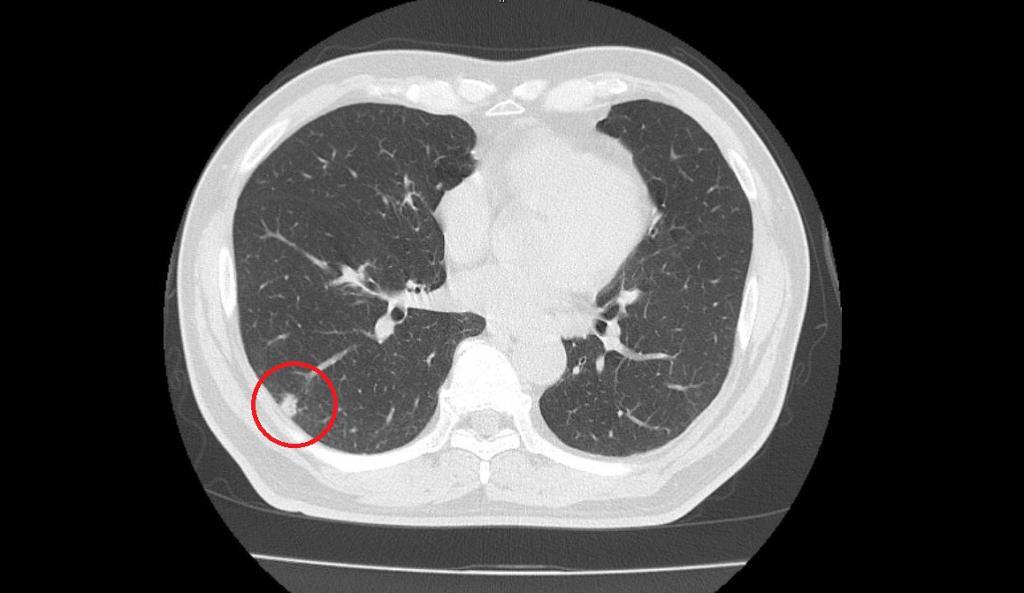

CTスキャンを用いた肺ドックは、そのような早期の肺がんを、非常に高い確率で発見することが可能です。